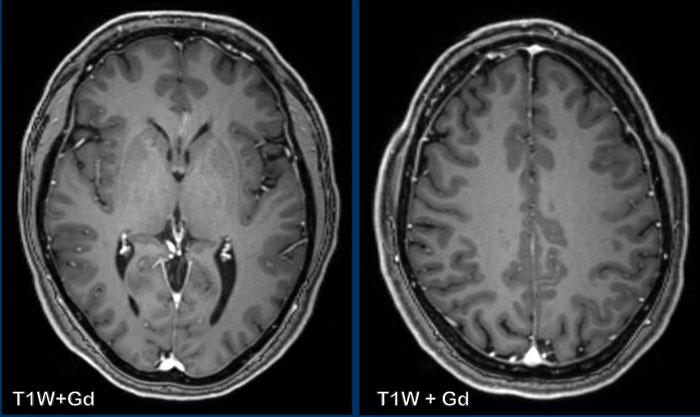

Các hình ảnh này của một bệnh nhân nam 58 tuổi nhập viện với triệu chứng đau đầu ở tư thế ngồi và đứng.

Hình ảnh

Có ngấm thuốc màng cứng đều đặn ở cả khoang trên lều và dưới lều.

Lưu ý các não thất nhỏ.

Tiếp tục với các hình ảnh mặt phẳng đứng dọc…